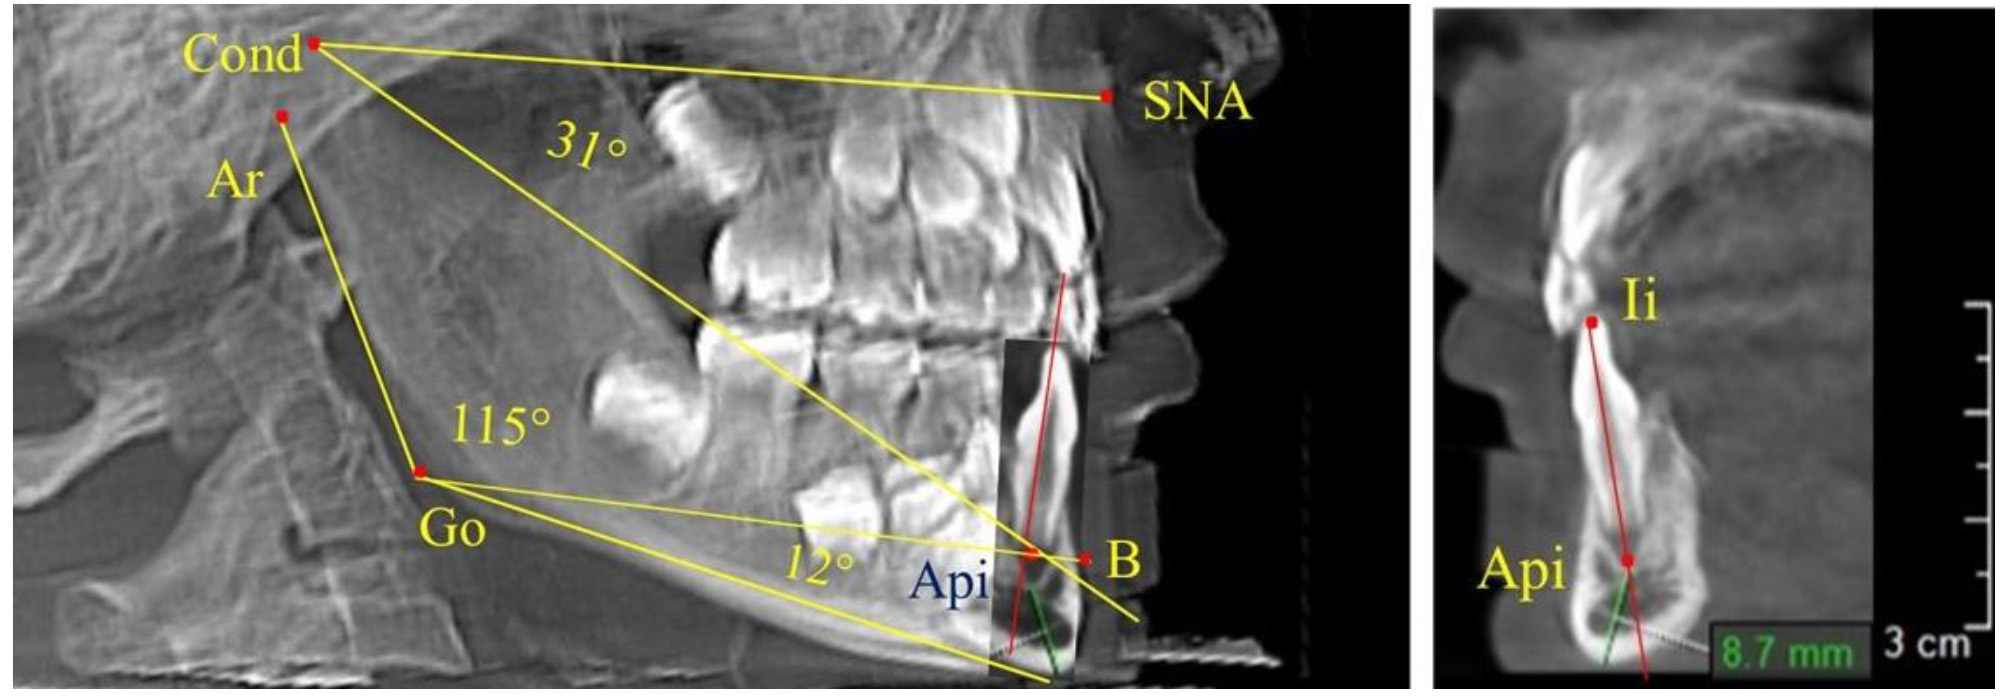

При анализе 16 рентгенограмм с аномалиями окклюзии в вертикальном направлении были выявлены признаки изменения основного гнатического угла. Так, для гнатических аномалий глубокой резцовой окклюзии/дизокклюзии (9 человек) отмечалось уменьшение угла гнатической части лица, величина которого была менее 26°. В то же время для гнатических аномалий (7 человек) вертикальной резцовой дизокклюзии («открытый» прикус) определялось увеличение угла гнатической части лица, который превышал значения в 33° (рис. 7).

Рис. 7. Варианты ТРГ при глубоком прикусе (а) и при открытом прикусе (б)

На представленных клинических примерах, несмотря на различия параметров основного угла гнатической части лица, определялись однотипные варианты угла нижней челюсти Ar-Go-Me и его составных частей Ar-Go-Api и Api-Go-Me.